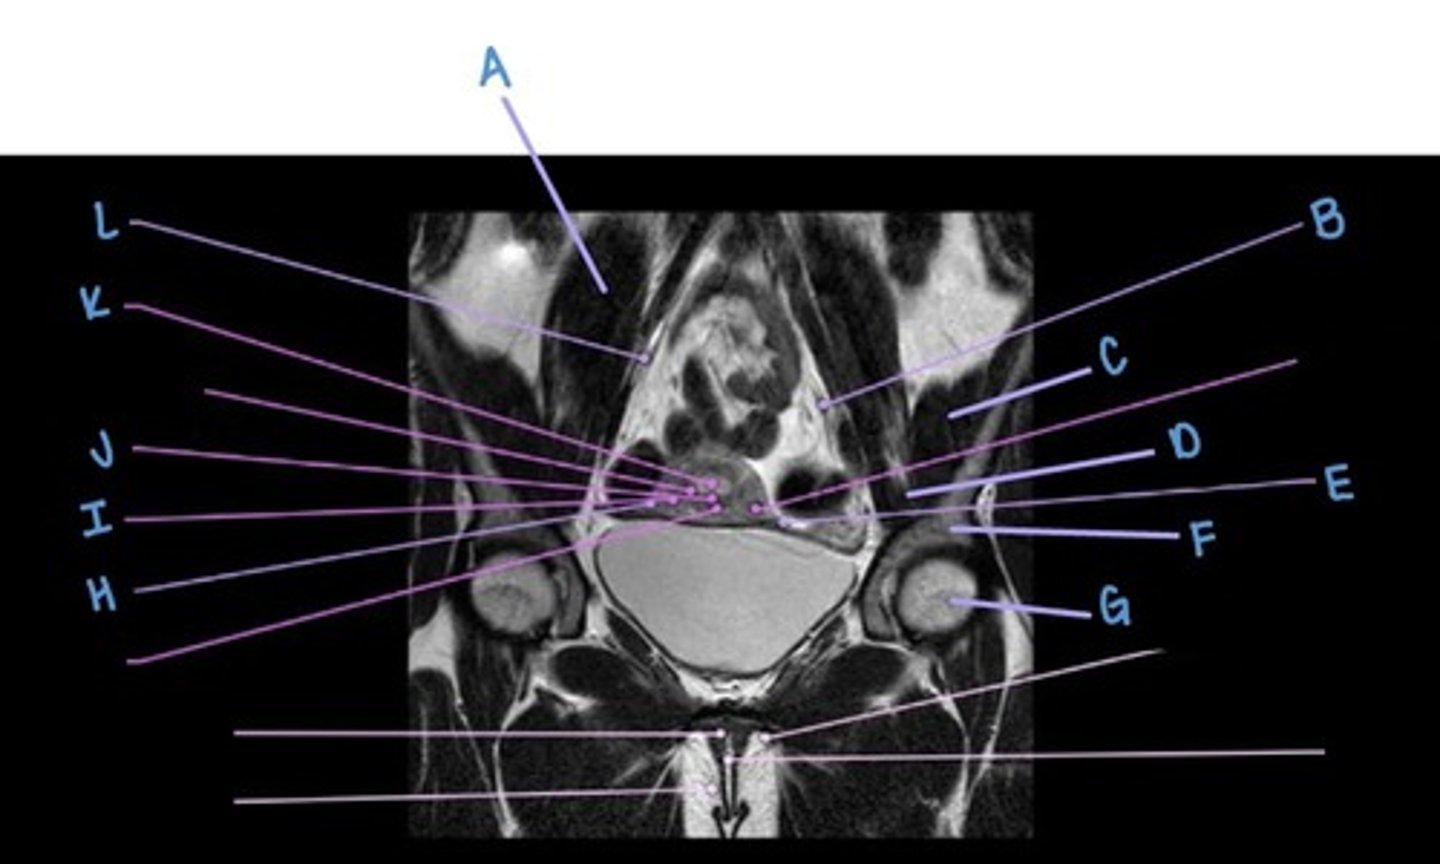

A

suspensory ligament of the ovaries

B & L

iliacus muscle

C

iliopsoas muscle

D

uterine (fallopian) tube

E & H

ilium

F

femoral head

G

myometrium

I

uterus

J

endometrium

K